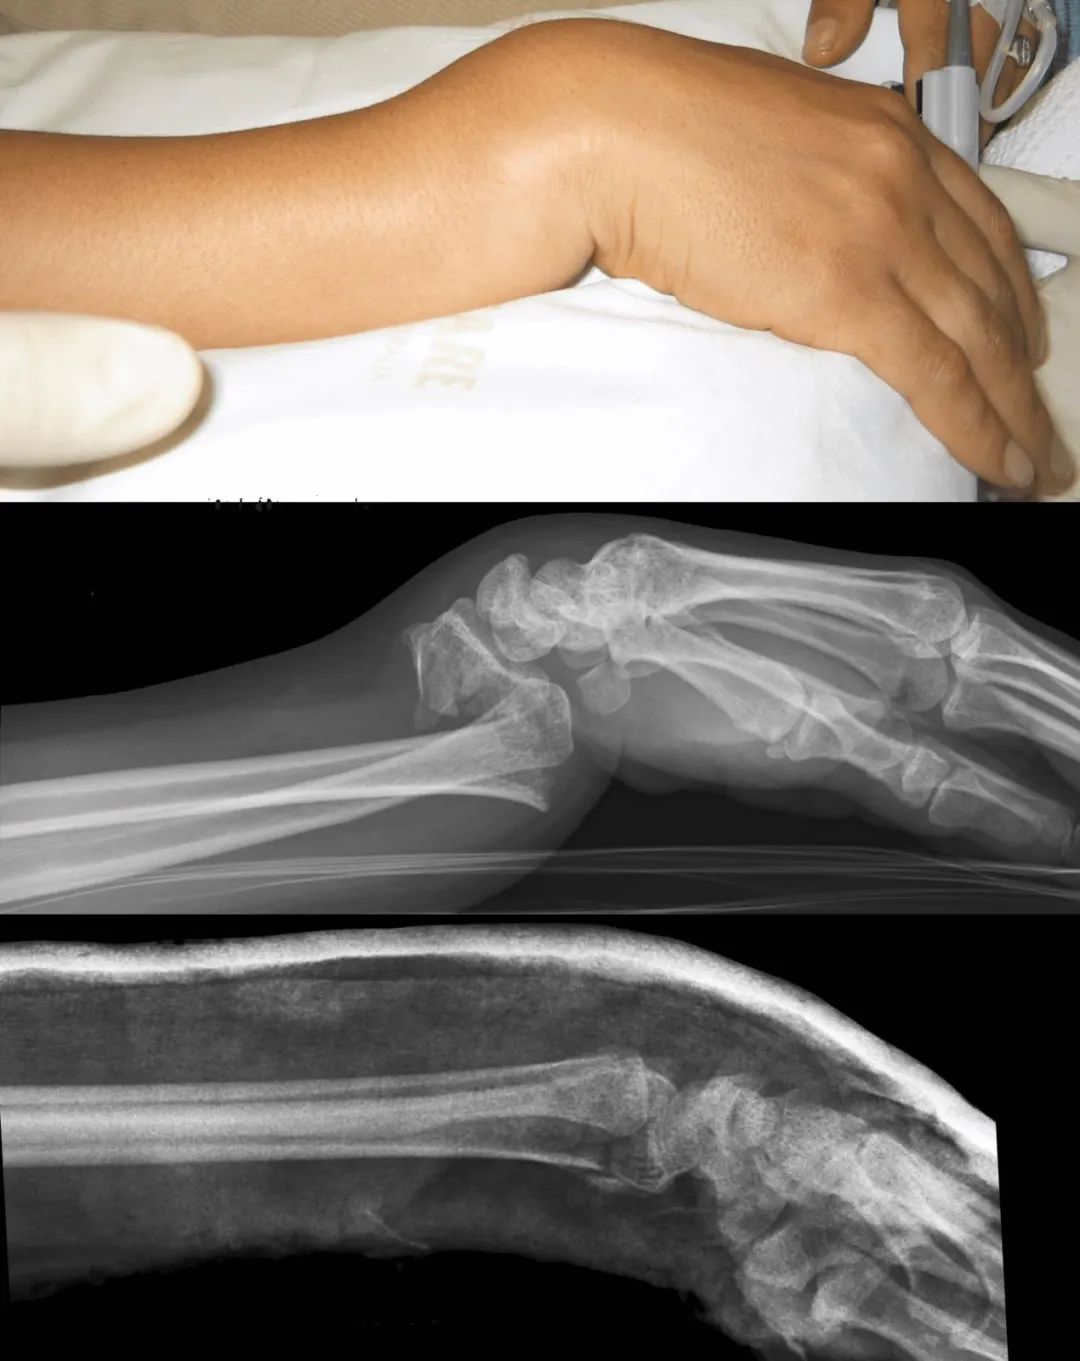

左右滑动查看更多

图源:https://litfl.com/moore-fracture/

大家都知道,我们摔倒下意识反应就是手撑地。如果是年纪比较大的老人,本身就有一些骨质疏松,摔的时候身体协调能力又不是很好,这个时候他手着地往下一戳,如果是往后手背先着地,叫 Smith 骨折;手心着地就容易出现 Colles 骨折,出现餐叉样畸形。如果骨折复位后感觉比较稳定,打石膏固定一段时间就可以,个别情况可能还需要手术复位。